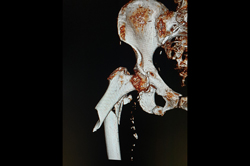

Subtrochanteric Fracture